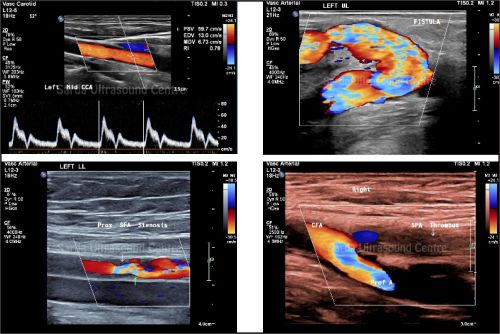

We provide state-of-the-art Doppler imaging to assess blood flow in various organs and detect abnormalities in vascular conditions, including deep vein thrombosis, arterial blockages, and other circulatory issues.

With vast experience in color doppler imaging in all the organ systems, high end machines, improved color flow pick up and advanced technologies like Microflow imaging; we provide most accurate and detailed results for better patient care and treatment planning.